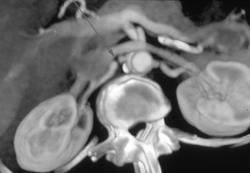

Renal Infarct Secondary to Aortic Aneurysm